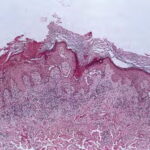

Histopathology. Focal acantholysis and dyskeratosis (focal acantholytic dyskeratosis) are present. Because these foci are small, they are sometimes found only when serial sections are obtained. The acantholysis may occur in four histologic patterns, resembling Darier’s disease , Hailey-Hailey disease, pemphigus vulgaris, or spongiotic dermatitis. Two or more of these patterns may be found in the same specimen. There is usually a superficial dermal infiltrate of lymphocytes and sometimes eosinophils. |

Ultrastructural Study. In the pemphigus-like zones, there is intradesmosomal separation, fewer desmosomes, and perinuclear aggregation of tonofilament bundles. In the Darier type, features similar to those of Darier’s disease are present. |